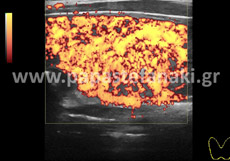

Triplex Αγγείων

Τα Τriplex αγγείων (φλεβών και αρτηριών), που πραγματοποιούνται είναι τα εξής :

Με την έγχρωμη υπερηχοτομογραφία (Triplex) μπορούμε να ελέγχουμε την ροή του αίματος μέσα στα αγγεία του σώματος όπως η αορτή, οι καρωτίδες, οι νεφρικές αρτηρίες, οι φλέβες και αρτηρίες άνω και κάτω άκρων